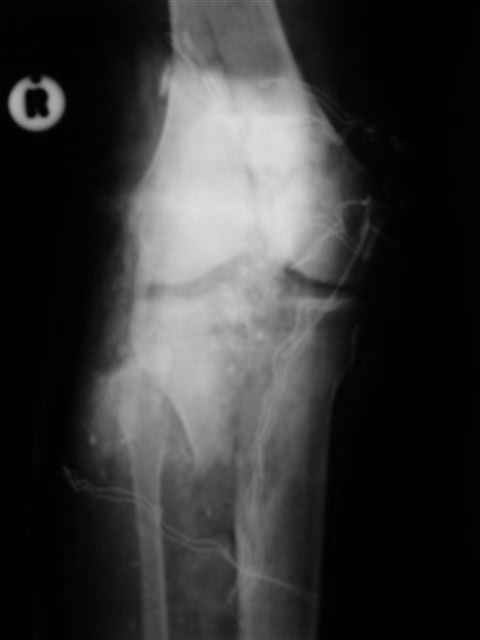

Спасибо за рекомендации. Сегодня взял больного на очередную хирургическую обработку и внешнюю фиксацию, картинки в приложении. При обработке опять иссекал ушибленные неркотизированные мышцы, частично кожный лоскут (явные признаки демаркации). связка надколенника разволокнена и выглядит едва ли жизнеспособной, пришлось частично убрать *лохмотья*.

Беда в том, что иссекая нежизнеспособные ткани происходит обнажение кости (рефиксироанная бугристость) м медиального края надколенника. Образовался обширный дефект наружной группы мышц. Литров 10 стерильного физ раствора извел на промывание раны. Заказал снимки, завтра поглядим.

Картинки по порядку: вид раны после первичной обработки, на следующий день и сегодня после

повторной обработки и внешней фиксации.

Вид раны на сегодня...

4 cутки после травмы.